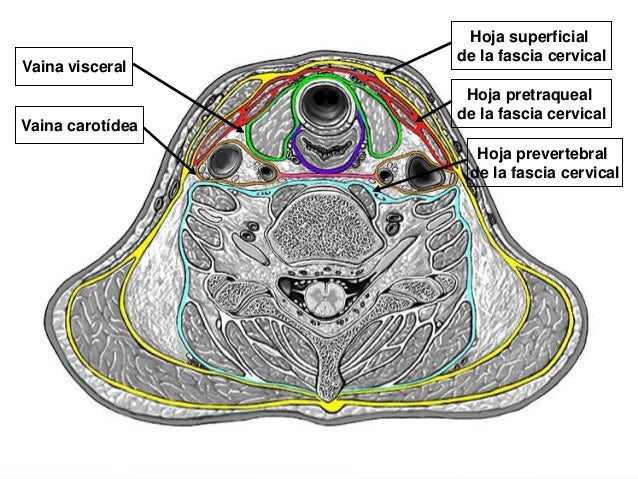

Antes que nada, es importante recalcar que la traquea se relaciona con otras estructuras mediante una vaina propia, que es una lamina de tejido conectivo que recubre a este órgano, esta vaina no es completa del todo, ya que se ve interrumpida por el paso de los vasos sanguíneos traqueales, inicia desde la parte superior rodeando a la porción inferior del cartílago cricoides, para luego descender y rodear al origen de los bronquios, quedando entre esta vaina los ganglios linfáticos traqueo-bronquiales.

También se relaciona con la hoja superficial de la fascia cervical, que se dirige transversalmente desde un esternocleidomastoideo hasta el otro, esta limita con la horquilla esternal al espacio de Gruber, esta se encuentra perforada en su parte media por las venas yugulares anteriores, que van de un plano superficial a un plano profundo.

Hoja pretraqueal de la fascia cervical, que se encuentra unida con la hoja superficial, se extiende de manera transversal, del musculo omohioideo al omohioideo del lado opuesto, envolviendo a los esternocleidomastoideos.